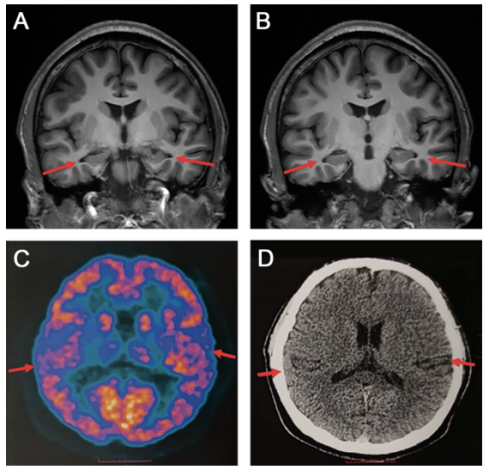

患者初诊时头颅磁共振.上海新华医院 供图

何阿姨脑部磁共振检查图,标识部分为脑囊虫头节.广医二院供图